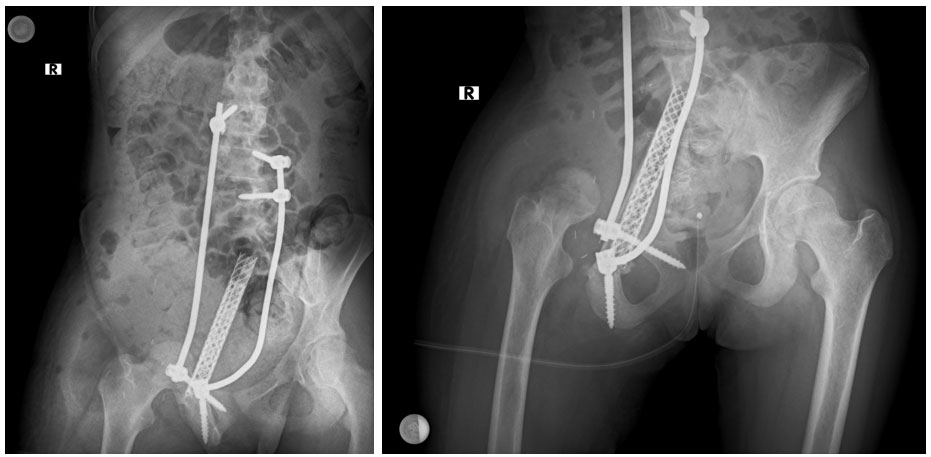

Ameliyat sonrası: Röntgende rezeksiyon sonrası rekonstrüksiyon işlemi görülmekte